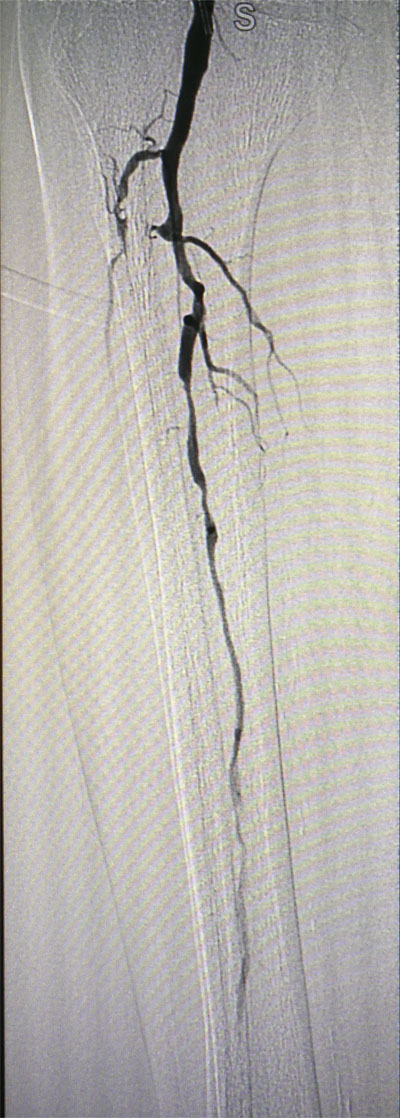

放射科导管室内做好了术前准备,患者由无创呼吸机及各种循环支持下开始介入手术,术中重症监护科严密观察患者的生命体征,内分泌科医生负责手术,患者下肢血流极差,膝下仅存一条多处严重狭窄的腓动脉供血,主要供血的胫前动脉及胫后动脉均长段闭塞,顺行穿刺成功后导丝下行困难,故采用踝下胫后动脉逆穿对接技术成功通过病变。经过近5个小时的奋斗,手术顺利完成,患者腓动脉及胫后动脉血流通畅,血流直达足底动脉环,患者感到足部逐渐温暖,术后清创时患者创面血流丰富。

治疗后